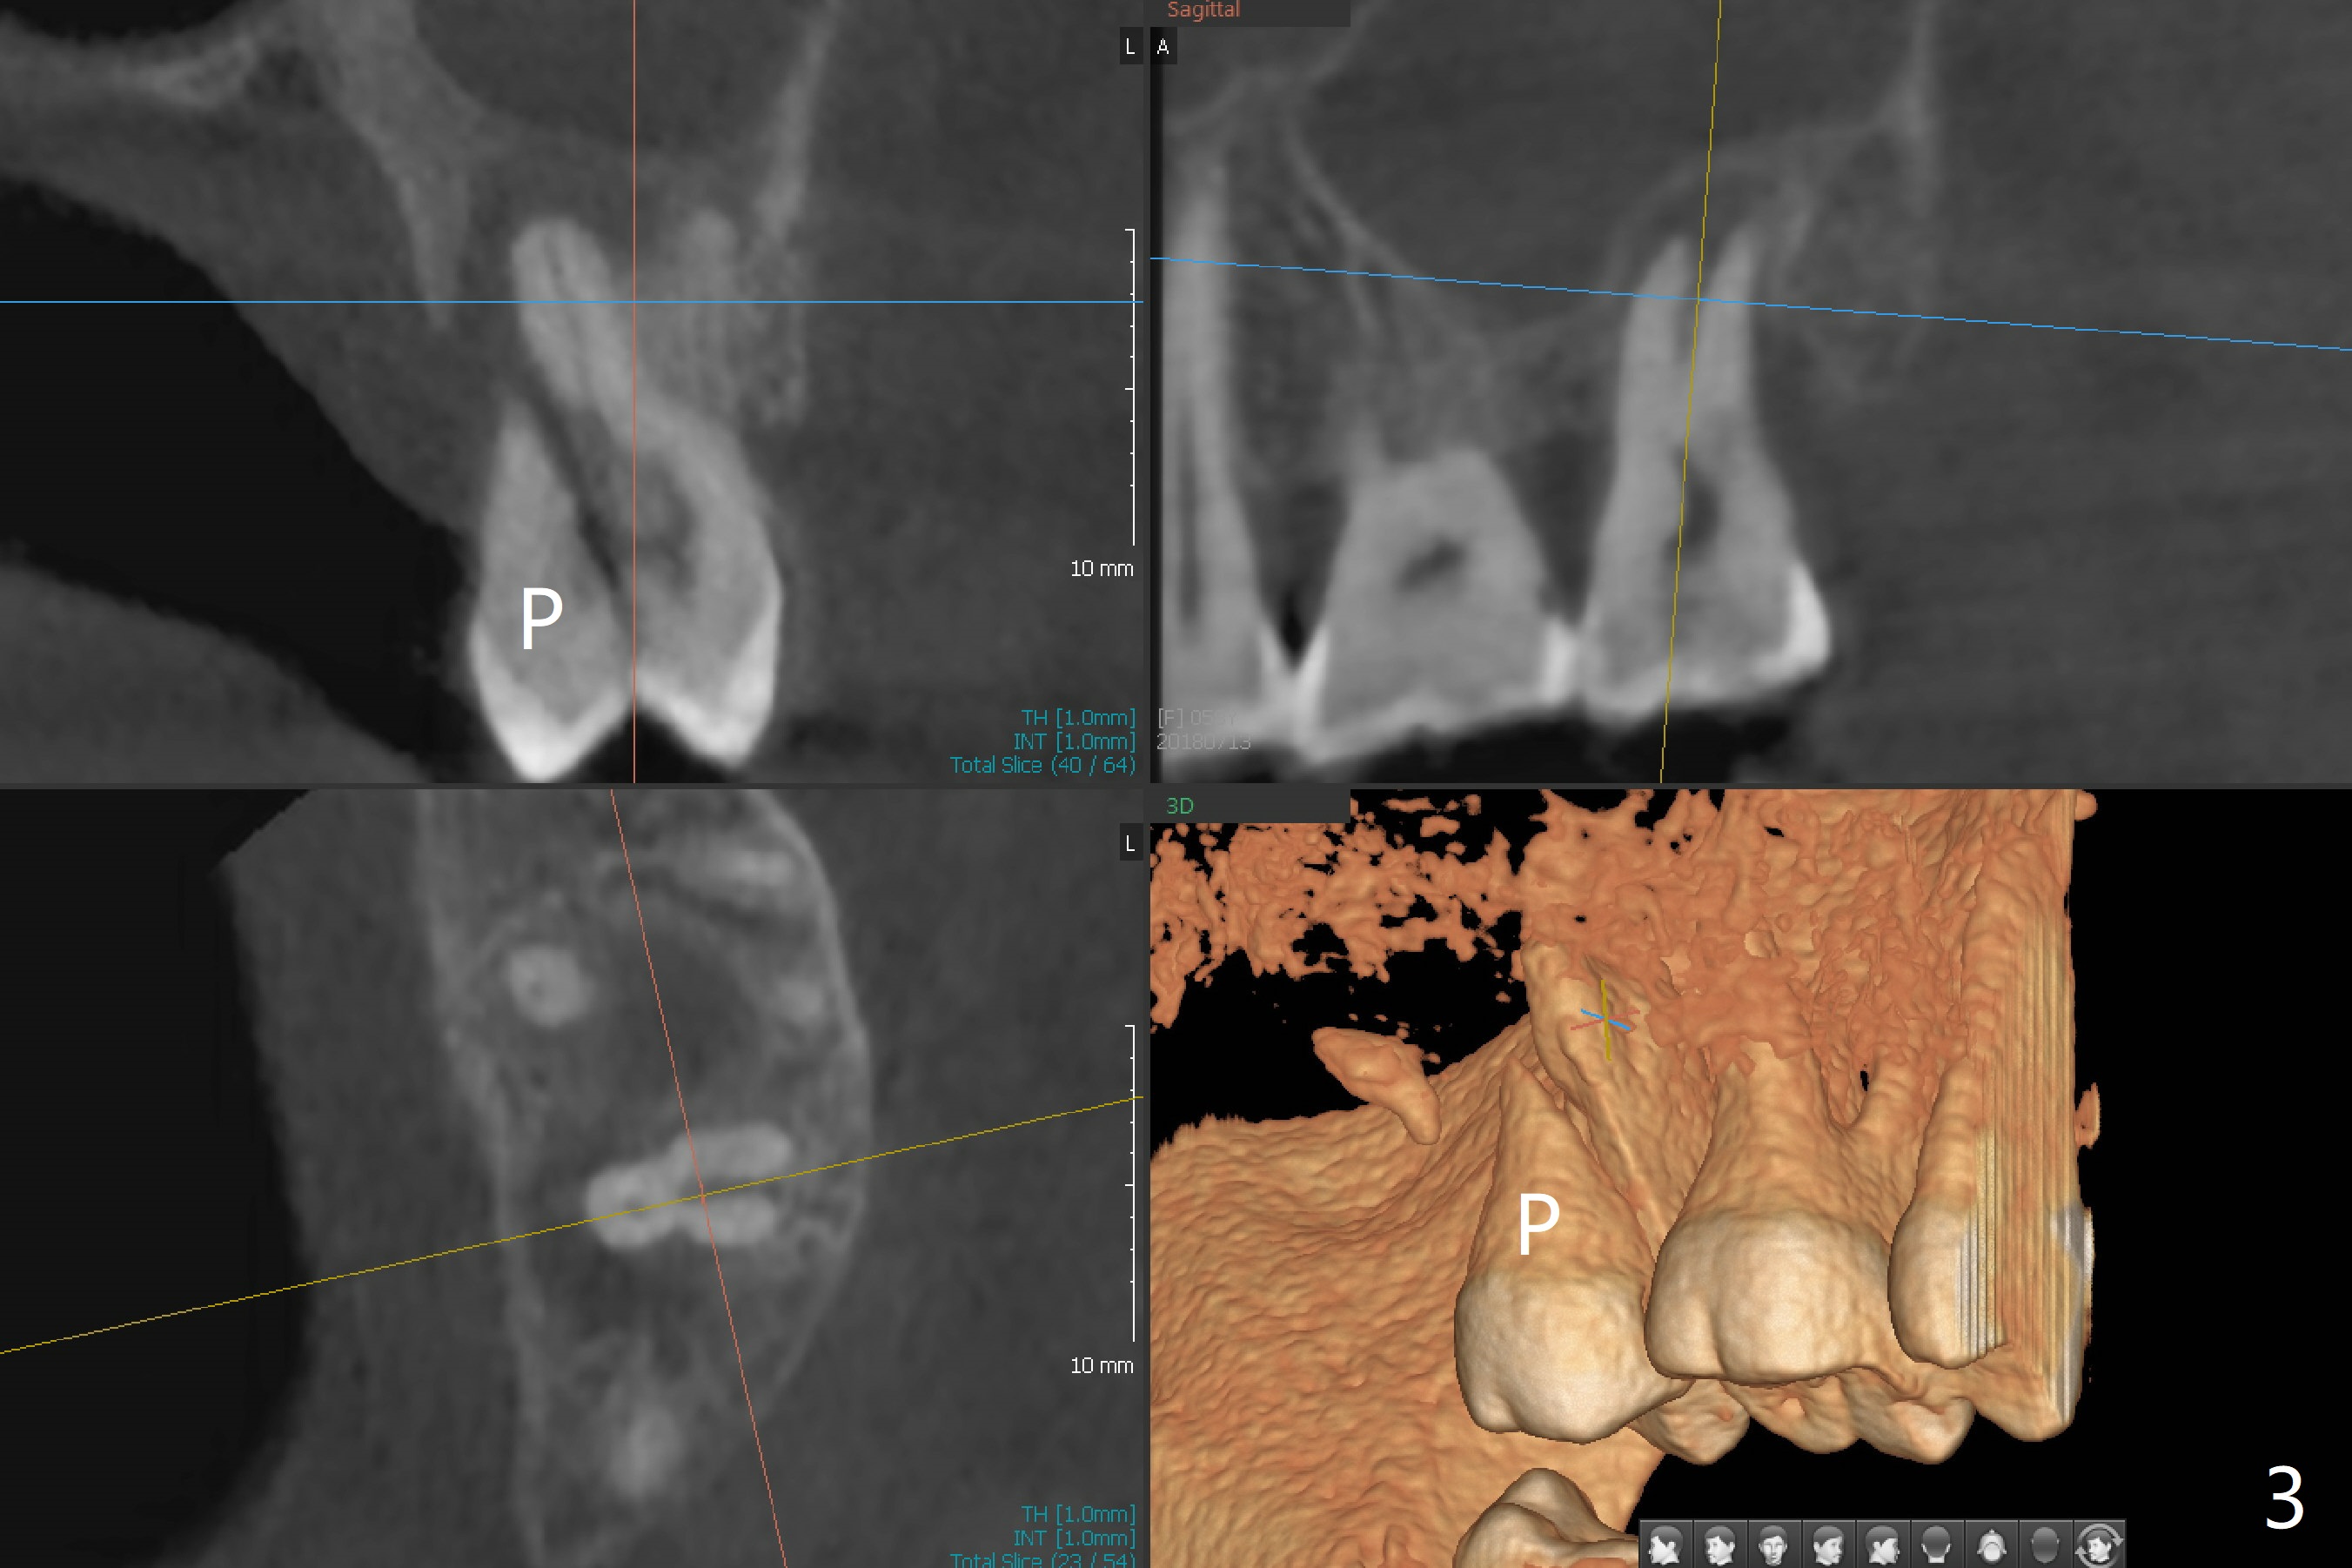

While the tooth #2 has a mesiodistal crack line with symptom (Fig.1 arrowheads, crown pending), the tooth #15 has a mesiodistal fracture (Fig.2). Immediately preop 5x5 cm CBCT (Fig.3) confirms the palatal (P) fracture with palatal bone loss. Although a 5x7.3 mm implant fits the site by design (Fig.4), a much longer implant is required to achieve primary stability past the sinus floor using IBS Magic Expanders (Fig.5,6 (20-30 Ncm; sinus lift with PRF membrane and allograft)). In contrast, primary stability could not be obtained by engaging dummy implant to the socket walls. A short implant without sinus lift is associated with less obvious complication such as fibrointegration. The implant seems osteointegrated 4.5 months postop (Fig.7). The abutment is changed to 6.5x4(5) mm before impression. There is no bone loss 5 months post cementation (Fig.8 (11 months postop)). It is the same 2.5 years post cementation (Fig.9,10).